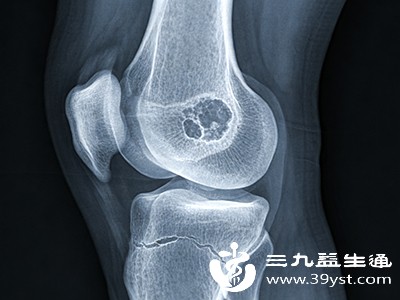

股骨头坏死是一种较为严重的骨骼疾病,若能在早期发现并及时治疗,往往能取得更好的效果。了解早期股骨头坏死的症状,对于我们及时察觉身体异常、采取相应措施至关重要。